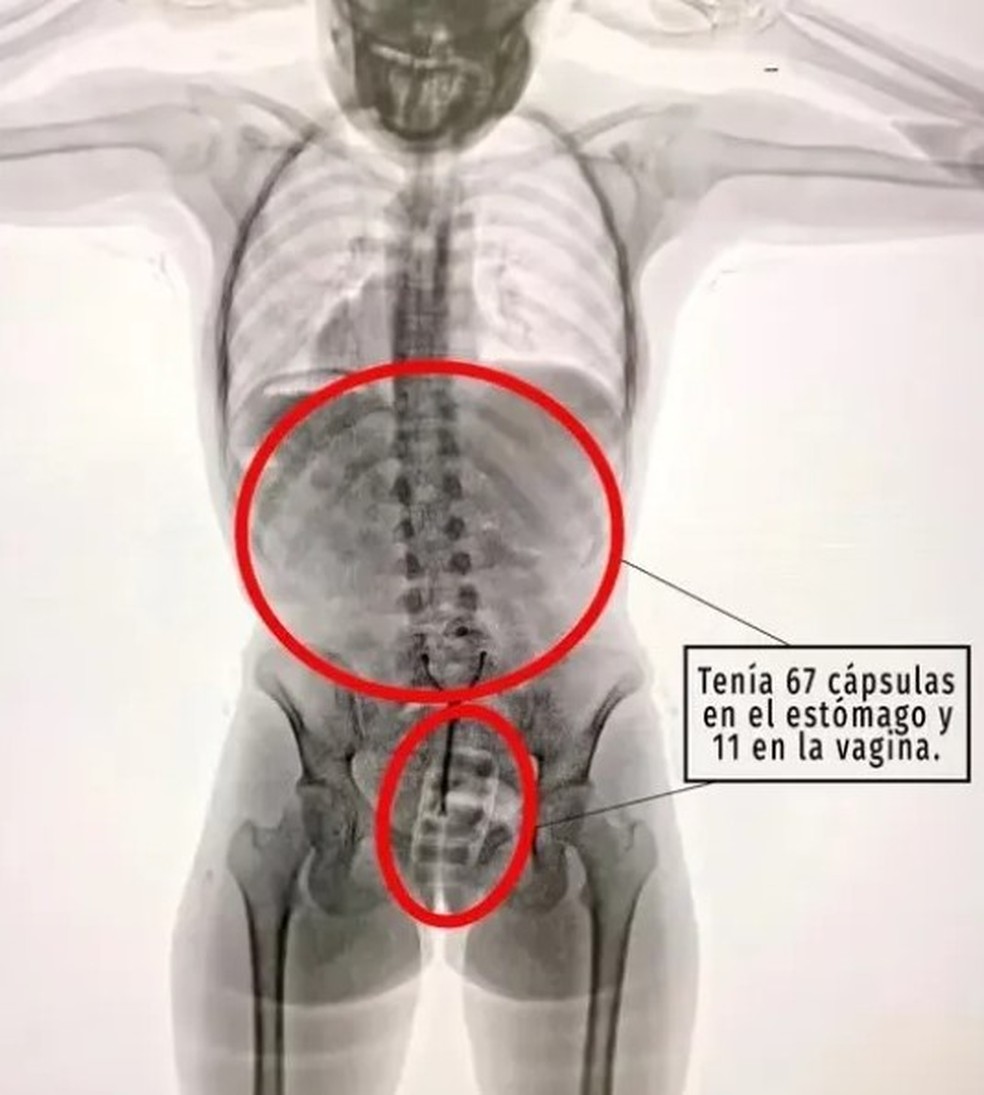

Uma jovem de 21 anos foi flagrada tentando contrabandear cocaína da Argentina para a Espanha. Ela colocou 11 cápsulas num preservativo e depois o inseriu na vagina. Ela também havia ingerido outras 67 cápsulas antes de ser parada no Aeroporto Internacional de Ezeiza, em Buenos Aires (Argentina) em 29 de julho, por agentes de segurança.

Os comprimido na sua vagina continham 110g da droga, com um valor estimado de R$ 34 mil em ruas das principais cidades da Europa. As cápsulas no estômago tinha cocaína avaliada em R$ 196 mil.